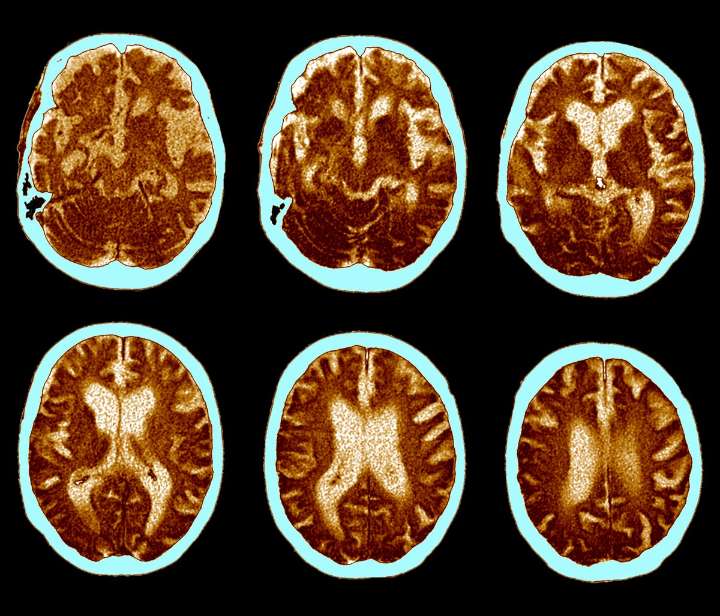

GLP-1 Pill Fails to Slow Alzheimer’s Progression in Clinical Trial

Top-line results from two large clinical trials by Novo Nordisk, the company behind Ozempic and Wegovy, found oral semaglutide failed to slow down Alzheimer's progression